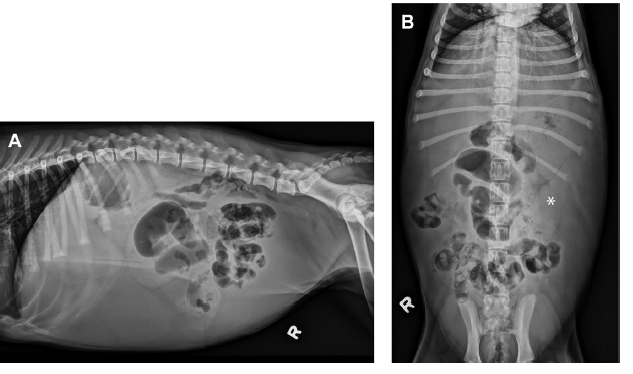

13y Fox terrier presented for vomiting, decreased appetite.

What are your findings? What’s your diagnosis? Recommended treatment?

Peritoneal fluid

Large, partially mineralized liver mass: Rule out neoplasia, abscess, hematoma, granuloma

Compartmentalized intestinal tract, surrounded by thick rim of tissue (capsule)

Recommendations: surgery to try and debride this encapsulation. Poor prognosis. Treatment: Steroids and tamoxifen to decrease fibrous formation.